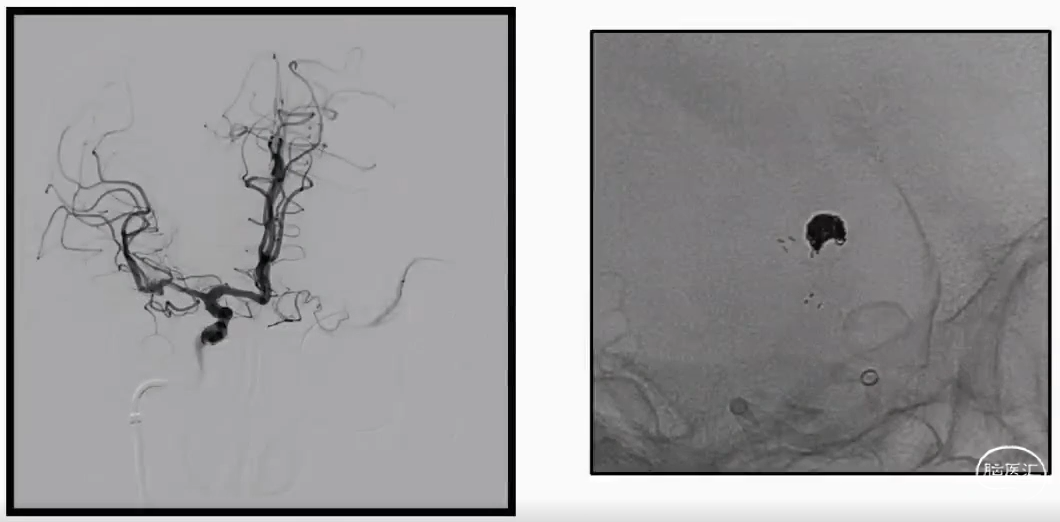

右侧桡动脉穿刺:6F桡动脉鞘

·造影:sim 2 造影导管、猪尾导管

·导丝:泥鳅导丝、加上加硬泥鳅导丝

·通路:6F 115cm 中间导管+加硬泥鳅导丝

·微导管:单根Echelon 10

·微导丝:Synchro 0.014

·弹簧圈:MicroVention

DSA:桡动脉入路+6F中间导管

术后:R-VA